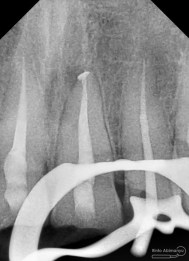

Oo iya tidak lupa juga dilakukan foto ronsen setelah pemasangan crown…

Dari foto ronsen terlihat gambaran yang “indah” dari mulai pengisian saluran akar yang rapat dan padat serta gambaran sementasi mahkota yang terlihat homogen….